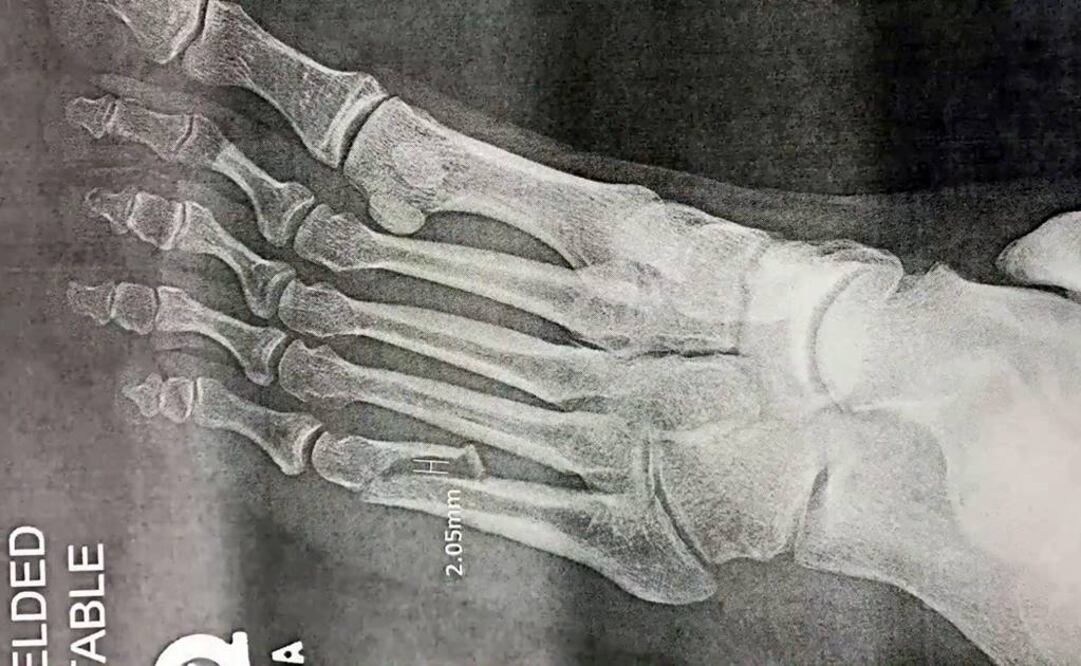

El cantante de la voz inconfundible anunció esta tarde que sufrió la fractura del quinto metatarso izquierdo y ya fue intervenido quirúrgicamente.

“Esto es lo que puede suceder cuando haces algo que no has hecho en casi 23 años”, tuiteó Rose esta tarde y compartió un video donde se observa a una especialista en traumatología explicando la radiografía de la lesión.

En el material se explica que el hueso del intérprete fue sometido a una reducción abierta y fijación interna, que consiste en colocar un fijador y tornillos (generalmente de titanio) para sujetar ambas partes del hueso de manera que queden alineadas y sanen sin necesidad de colocar un yeso.